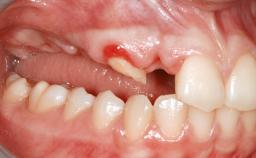

Le Fort I Interpositional Graft and Mandibular Sandwich Osteotomy for Maxillofacial Rehabilitation after Severe Periodontitis

A 47-year-old woman who had suffered from aggressive periodontitis requiring a number of periodontal interventions over more than 10 years was referred by her general dental practitioner and periodontologist for bone augmentation and implant therapy. Her failing dentition had already been scheduled for extraction. The patient expressed a desire for implant-supported fixed restorations and esthetic improvement of her lower face. She had agreed to consult with a maxillofacial surgeon after the referring dentist had suggested bone augmentation. An initial examination by the maxillofacial surgeon revealed mobility of all residual teeth in a patient who was very unhappy with the function of her removable partial dentures. Due to periodontally migrated flaring teeth and loss of occlusal support, the vertical dimension of occlusion was dramatically reduced. The patient was displeased with her lower face because of deepened nasolabial, commissural, and supramental folds.